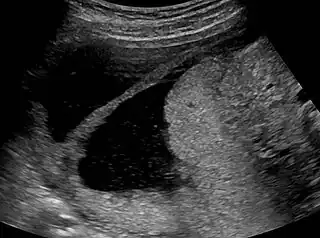

The history of a pregnancy event followed by a D&C leading to secondary amenorrhea or hypomenorrhea is typical. Hysteroscopy is the gold standard for diagnosis.[13] Imaging by sonohysterography or hysterosalpingography will reveal the extent of the scar formation. Ultrasound is not a reliable method of diagnosing Asherman's Syndrome. Hormone studies show normal levels consistent with reproductive function.

-

Ultrasound view. -